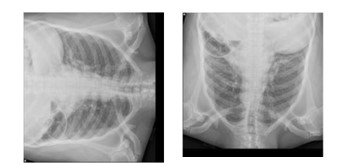

The lungs radiography (chest x-ray) is a screening tool for COVID-19 that is widely used; however, its interpretation can be difficult due to the presence of subtle changes in the lungs caused by the virus, which can be seen in the images. This is the case even though the lungs radiography is widely used. In this article, we present a CNN model that can be utilized for the classification of data derived from lungs radiography. The proposed model was tested and refined using a series of lungs radiography taken from patients diagnosed with COVID-19. When it came to the classification of the data, the findings of the research showed that the CNN model performed significantly better than the conventional approaches did. The accurateness of the anticipated model was found to be 96.2% while its sensitivity was found to be 96.8%. It was demonstrated that it had the potential to be utilized for the purpose of classifying the data associated with the presence of COVID-19. In addition, radiologists can use it to help them interpret the lungs radiography that have been taken.